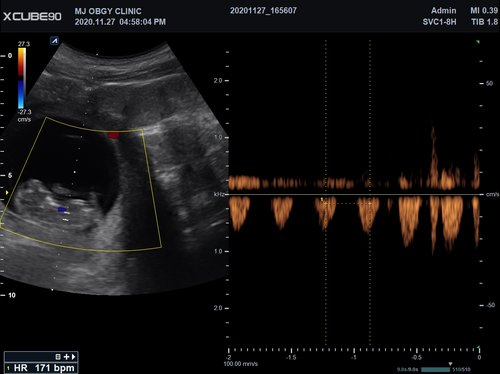

Volumen Konvex-Sonden

• SVC1-8H (1-8 MHz) für Ultraschalluntersuchungen in Bereichen Abdomen, Geburtshilfe, Gynäkologie, Urologie, Pädiatrie, EM